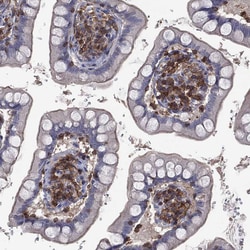

Invitrogen™ DOCK8 Polyclonal Antibody

Brand: Invitrogen™ PA5140262

Gently mix before use. Optimal concentrations and conditions for each application should be determined by the user. Immunogen sequence: INRYSSAEIR KQFTLPPNLG QYHRQSISTS GFPSLQLPQF YDPVEPVDFE GLLMTHLNSL DVQLAQELGD FTDDDLDVVF Highest antigen sequence indentity to the following orthologs: Mouse - 88%, Rat - 86%.

The Dedicator of cytokinesis protein 8 (DOCK8) is a member of the DOCK180 family of guanine nucleotide exchange factors. DOCK8 plays an essential role in humoral immune responses and is important in the proper formation of the B cell immunological synapse. Mutations in this gene result in the autosomal recessive form of the hyper-IgE syndrome.

| Immunohistochemistry (Paraffin), Western Blot | |

| Recombinant protein corresponding to Human DOCK8. Recombinant protein control fragment (Product #RP-109342). | |